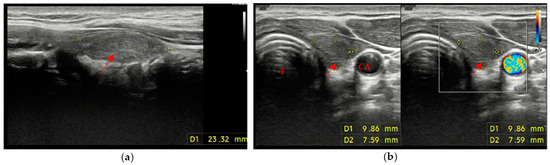

• A mildly hypoechoic or isoechoic pattern with ill-defined margins was found in 23 patients, which is approximately 58% of patients with evidence of residual swab (Figure 2a,b).

Figure 2. Residual swab pattern (red arrow) 2, characterized by a mildly hypoechoic/isoechoic ecostructure and ill-defined margins; (a) Longitudinal view; (b) Axial view. No vascular signal is seen at Color Doppler. Carotid artery (CA) and Trachea (T).